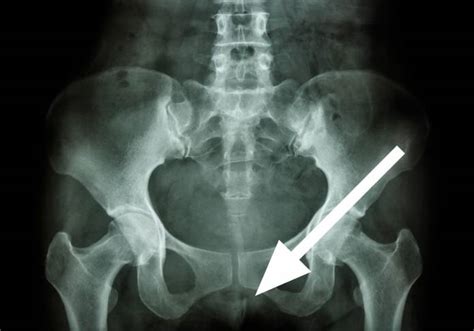

Definitionsgemäß muss eine Steißbeinprellung jedoch nicht mit sichtbaren Hautverletzungen einher gehen Zudem kann es in manchen Fällen sogar zu chronischen Schmerzen in diesem Bereich kommen. Steißbeinprellung oder Steißbeinbruch? Sowohl ein Steißbeinbruch als auch die Prellung des Steißbeines gehen in den meisten Fällen mit starken Schmerzen im unteren Rücken und Gesäß-Bereich einher, denen man ohne weiteres „ausgesetzt" ist

Auch Sportverletzungen und Sportunfälle können dazu beitragen, dass es zu einer Steißbeinprellung kommt. Ausnahmen bilden offene Brüche, bei denen Knochensplitter aus einer offenen Wunde herausragen, und frei bewegliche Knochenfragmente, die sich als isolierte Körper unter der Haut ertasten lassen